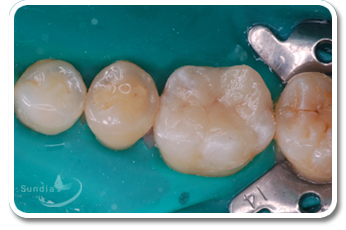

| ◆全瓷嵌體、覆體案例分享 |

| (圖片由 宋文傑 醫師提供) |

| 患者第二小臼齒有深度蛀牙,建議使用嵌體,使填補區域能緊密與牙齒貼合,減少敏感,以及恢復美觀與功能。 |